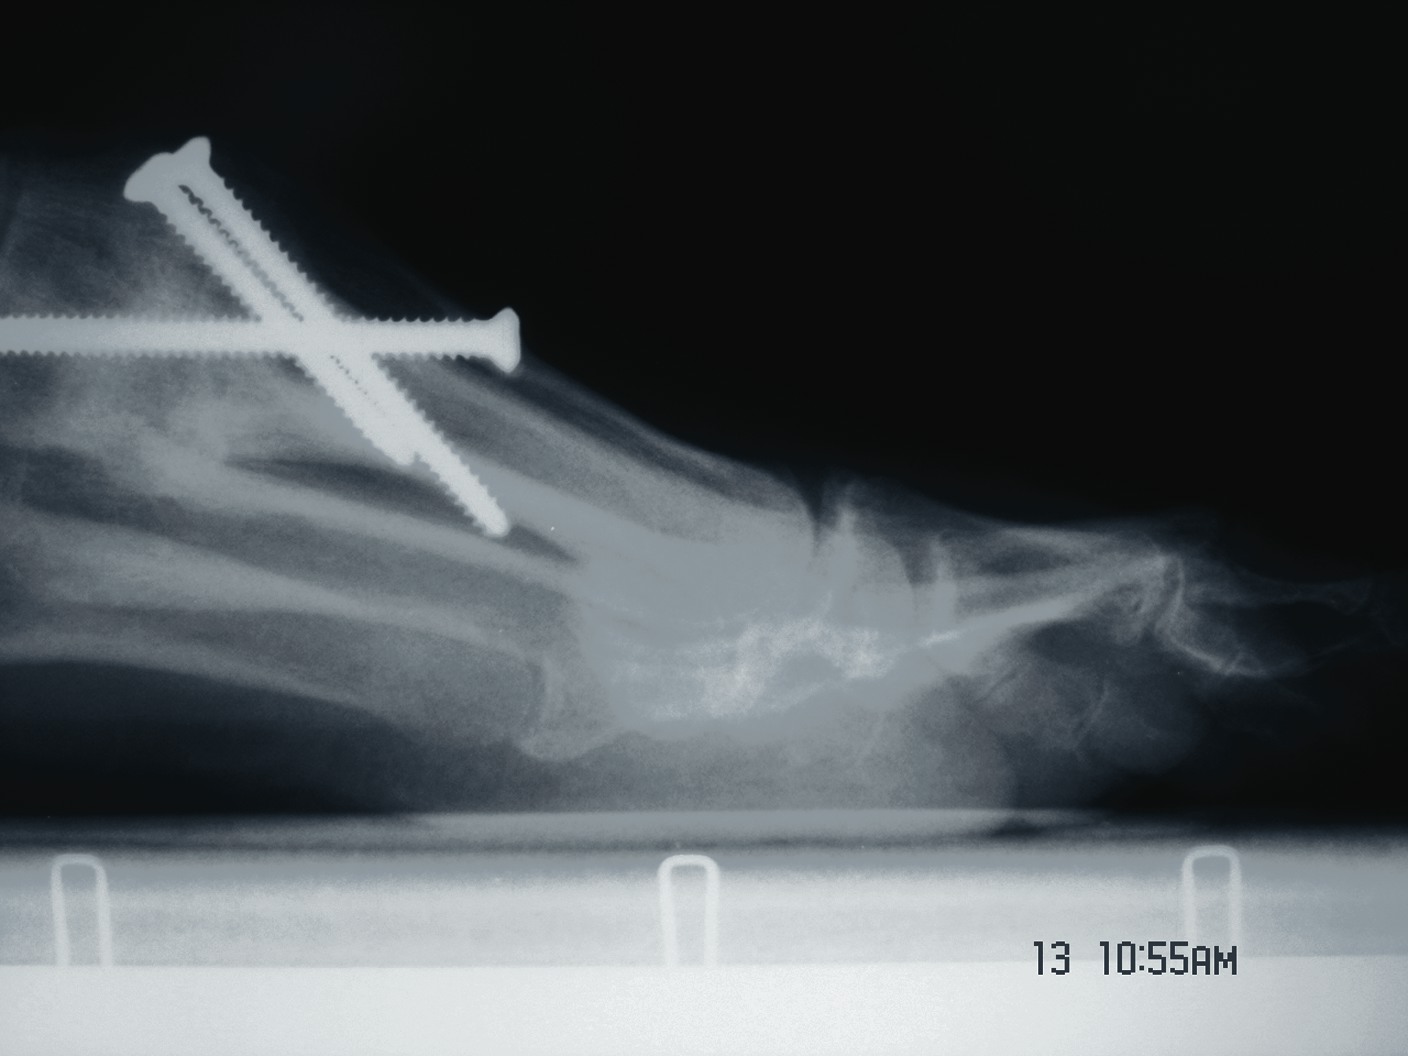

One should place the patient into a supine position and utilize a tourniquet. Evaluate post-anesthesia assessment of the first MPJ range of motion. Manually distract the first MPJ and plantarflex the first metatarsal. Dorsiflex the hallux to determine the obtainable first MPJ range of motion and evaluate for crepitus. If there is first ray hypermobility and no crepitus, one may be able to salvage the first MPJ by translating the first ray plantarly and stabilizing the medial column. Initially, surgeons should address contributing global pathology. Then proceed to the first ray and make a dorsomedial skin incision spanning the first MPJ. Retract the neurovascular structures. Make a longitudinal incision to bone, spanning the distal one-third of the first metatarsal and proximal one-half of the proximal phalanx. Evaluate the adjacent cartilage and make a critical decision to preserve or destroy the joint. It is important to realize that evaluation of cartilage quantity and quality via direct intraoperative visualization weighs heavily upon the final decision to perform a joint preservation or destructive procedure. One should strongly consider joint destructive procedures if greater than 30 percent of the dorsal portion of the first metatarsal head presents as grade III to grade IV chrondromalacia. One must independently evaluate grade III and IV chrondromalacia and osteochondral defects in the remaining 70 percent of the metatarsal head. Small cartilage lesions may yield themselves to debridement, drilling or OATS procedures whereas large cartilage defects will likely result in arthrodesis. If the joint is salvageable and one identifies first metatarsocuneiform hypermobility, perform a cheilectomy and a subsequent, sagittal Lapidus procedure. If one identifies hypermobility or posttraumatic first metatarsal angular pathology, correct it after completing the first MPJ soft tissue and osteophyte debridement. If one decides to perform arthrodesis on the joint, debride identified osteophytes, loose bodies, synovitis and scar tissue. Denude the adjacent cartilaginous surfaces to the healthy level of bleeding bone via curettage or via convex distal and concave proximal reamers. Fenestrate the adjacent bone surfaces with a 1.0- or 1.5-mm drill bit. Temporarily fixate the hallux by utilizing two K-wires in the desired position. The position should be approximately 20 to 30 degrees dorsiflexed in relation to the first metatarsal declination; abducted and parallel to the second digit; and with the nail void of frontal plane varus or valgus rotation. Obtain an AP radiograph to evaluate the bony apposition and alignment of the proposed first MPJ arthrodesis. Also obtain a lateral radiograph with the foot loaded in order to evaluate the hallux and its relationship to the first ray. After obtaining the desired position, utilize two fully threaded (3.5 or 4.0) crossing cortical screws for permanent fixation. Place the first screw from proximal medial to distal lateral and place the second screw from distal medial to proximal lateral across the first MPJ. Ensure the screws do not cross at the level of the joint. Use a 3.5-mm burr to create a dell in the cortical bone where the head of the screws engage the bone as Manloli and Hansen have described.48 After obtaining rigid internal fixation across the first MPJ, utilize a shear strain autograft (harvested via a percutaneous calcaneal grafting technique) at the arthrodesis site.57 Place the autograft in two troughs created by the 3.5-mm burr at the arthrodesis site. Use a bone mallet and tamp to provide a press fit.58